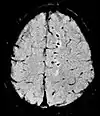

Diffusion weighted (DWI)ConventionalDWIMeasure of Brownian motion of water molecules.[66] High signal within minutes of cerebral infarction (pictured).[67]

Apparent diffusion coefficientADCReduced T2 weighting by taking multiple conventional DWI images with different DWI weighting, and the change corresponds to diffusion.[68] Low signal minutes after cerebral infarction (pictured).[69]